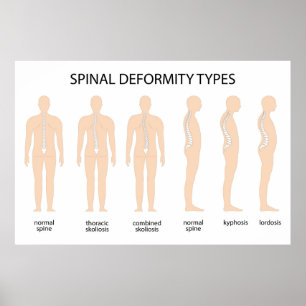

Anatomie der Wirbelsäulenfehlbildung Poster

PreisCHF 153.00